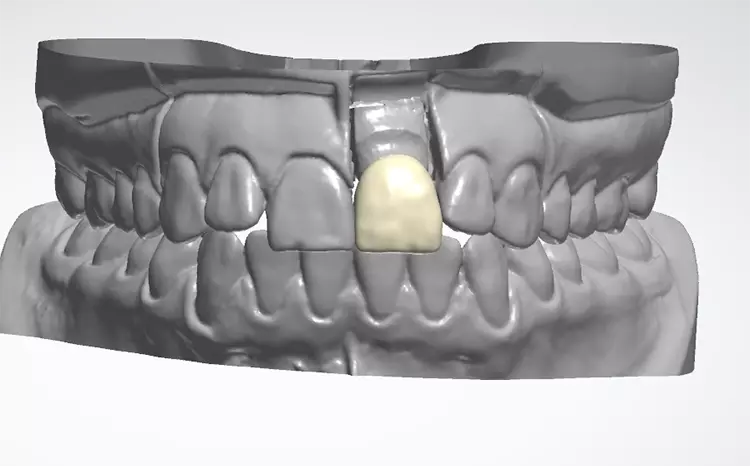

Die Auswahl des Materials für die definitive Krone wurde in Rücksprache mit dem Zahntechniker getroffen. Sie erfolgte nach der Herstellung der Arbeitsmodelle, der Beurteilung der Platzverhältnisse, der Stumpffarbe und der definierten Zielfarbe. Aufgrund des verfärbten und devitalen Zahnes und zur Vermeidung des „Grauschleiers“ galt es, ein Material mit weniger Transluzenz als Lithiumdisilikat zu verwenden.

Es sollte ein Zirkonoxidmaterial mit hochästhetischen Eigenschaften zum Einsatz kommen. Die Wahl fiel auf IPS e.max ZirCAD Prime, ein Werkstoff der zwei Zirkoniumdioxid-Rohstoffe kombiniert: im Dentinbereich ein 3Y-TZP-Zirkonia mit hoher Festigkeit (1.200 MPa Biegefestigkeit) und im Schneidebereich ein transluzenteres 5Y-TZP-Zirkonia (650 MPa Biegefestigkeit). Der stufenlose Farb- und Transluzenzverlauf in den Materialscheiben ist ein zusätzlicher Vorteil für derartige Restaurationen im sichtbaren Bereich.